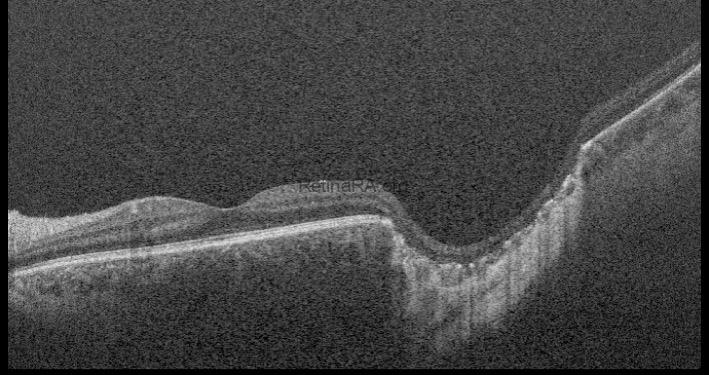

Optical coherence tomography (OCT) through the lesion reveals a large, excavated, coloboma-like chorioretinal defect located temporal to the fovea.